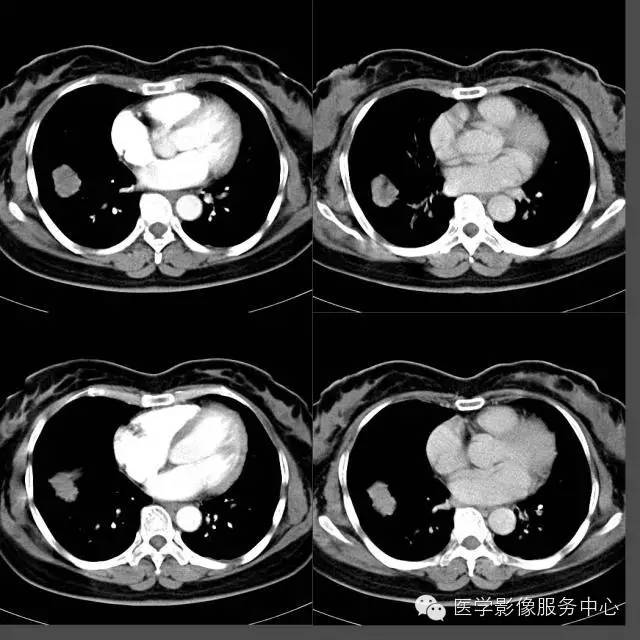

【病例】右下肺乳头状腺癌1例CT影像表现

女,49岁, 咳嗽、胸痛一周。

CT上表现的结节或肿块影像在病理组织学上为肿瘤的乳头状结构,以及破坏、扭曲的肺组织;磨玻璃样阴影代表肿瘤细胞沿肺泡壁生长或阻塞肺泡腔引起的阻塞性肺炎;

肺乳头状腺癌生长方式与肺泡癌相似,结节或肿块影周围出现的卫星灶能对应病理组织学上的阻塞性肺炎、支气管炎、细支气管脓肿等改变。这种磨玻璃样改变在肺腺癌病例中普遍可以看到,但在其他类型肺癌中比较少见。

“空泡征”、“空气支气管征”在肺乳头状腺癌病例中大部分可以看到,但边缘光滑、境界清楚;而其他类型肺癌即使出现这些征象,其边缘境界往往不清楚,这一点是和其他类型肿瘤所不同的。